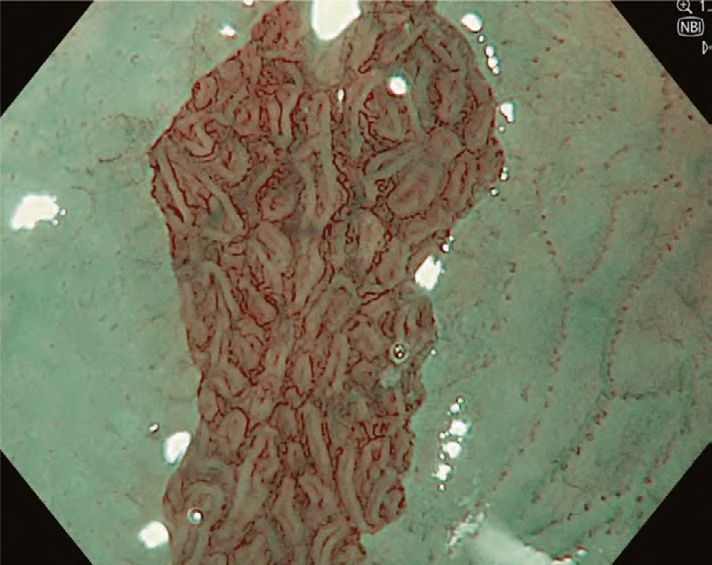

Mucosal and vascular patterns in each NBI image were classified as “regular” or “irregular” based on characteristics agreed upon by the working group (Table 1). Regular mucosal patterns were marked by circular, ridged/villous, or tubular patterns, and irregular mucosa was marked by absent or irregular surface patterns (Fig. 1a, b). Regular vascular patterns were defined by blood vessels situated regularly along or between mucosal ridges and/or those showing normal, long branching patterns; irregular vascular patterns were marked by focally or diffusely distributed vessels not following the normal architecture of the mucosa (Fig. 1c, d). Images not readily identified as regular or irregular were deemed uncertain.